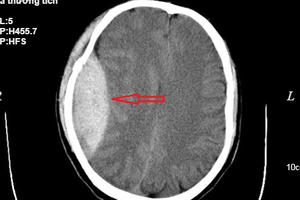

Bé 14 tháng tuổi bị bảo mẫu bạo hành, ném mạnh xuống nền nhà đã qua đời do chấn thương sọ não quá nặng, sau nhiều ngày các bác sĩ nỗ lực cứu chữa.

Sau gần hai tuần điều trị, bệnh nhi đang được theo với tình trạng rất nặng, hôn mê sâu, chết não, tiên lượng tử vong.